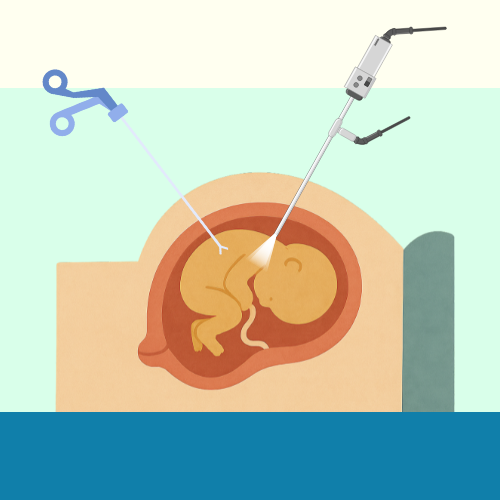

4. Advanced Fetal Intervention Therapies

In some pregnancies, diagnostic results may reveal fetal conditions that can be treated before birth. Fetal intervention therapies such as intrauterine transfusions, fetal shunt placements, or laser procedures for twin-to-twin transfusion syndrome (TTTS) can significantly improve survival and long-term health outcomes.

When Are Fetal Interventions Advised?

Interventions are recommended only after detailed evaluation and counselling by a multidisciplinary fetal medicine team. Each decision is based on gestational age, fetal condition, and overall prognosis to ensure both mother and baby receive the safest and most effective care.